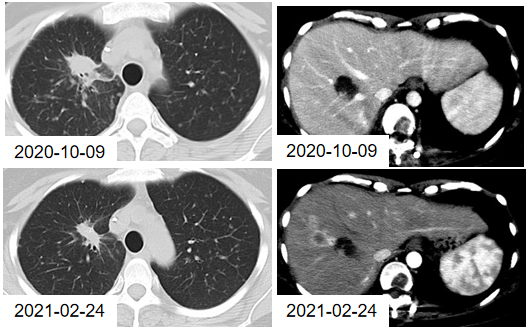

图7. 2020年8月31日与10月9日的CT检查结果

2021年1月18日、2021年2月8日,患者接受2周期的贝伐珠单抗联合免疫治疗维持治疗,具体方案:贝伐珠单抗 500mg 静滴 d1 + 替雷利珠单抗 200mg 静滴 d1 q3w。2021年2月24日,影像学评估示:肺部病灶缩小,肝新发病灶。

图8. 2020年10月9日与2021年2月24日的CT检查结果